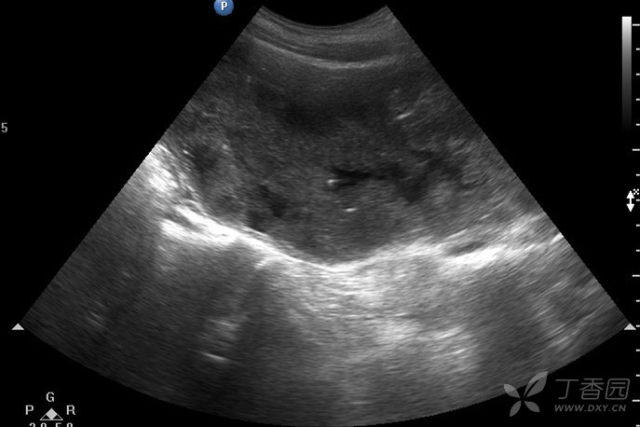

(ˉ▽ˉ;) 多学科团队合作 湖南省妇幼保健院助力肾积水新生儿重获健康2024年11月,张女士因胎儿双侧输尿管扩张合并肾积水在湖南省妇幼保健院进行了剖宫产手术,手术过程顺利,但因为宝宝的特殊情况给这个新生命的家庭蒙上了一层阴霾。接收患儿后,新生儿二科医护人员迅速启动评估流程,包括详细的病史收集、体格检查和必要的辅助检查。同时,医护人...